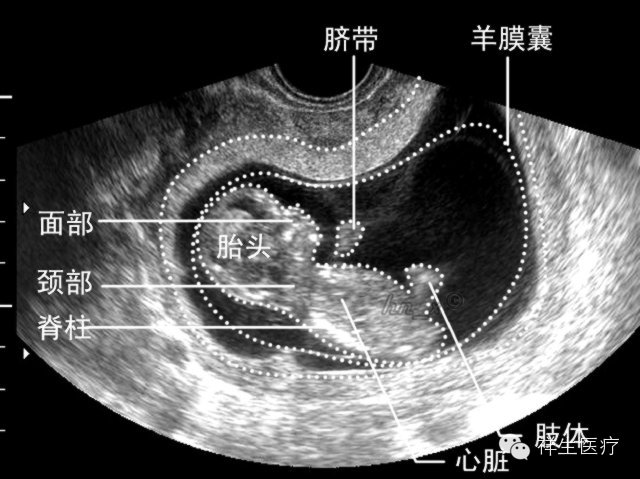

5.孕9周:此时开始称为胎儿。各部分发展趋于完善,经阴道超声扫查已能观察大部分结构。

6.孕10周:这时候可以看见宝宝颈背部的皮肤级皮下组织啦,还可以数出宝宝的手指,肢体活动相当活跃。

7、孕11-12周:可以分辨宝宝脊柱,头面耳廓开始显现,外生殖器开始发育,但是不能辨别男女。可以诊断一些明显畸形(例如无脑儿)